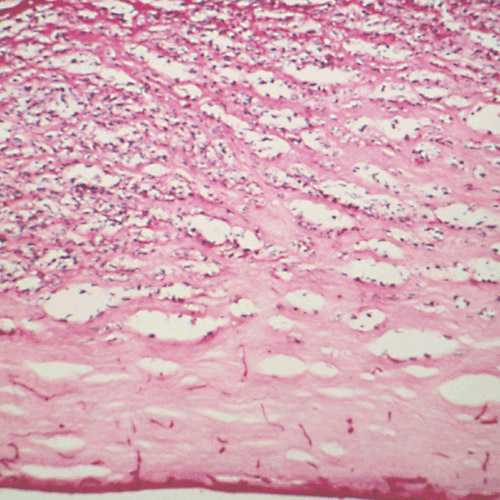

The pathology of pulmonary disorders due to Aspergillus spp.

Kradin RL, Mark EJ.

Arch Pathol Lab Med.

2008 Apr;132(4):606-14